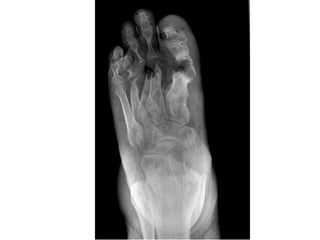

• Long standing ulcer = osteomyelitis may be

there

• Long standing ulcer = foreign body is

suspected